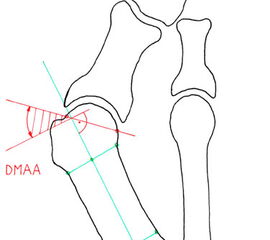

Hallux valgus Operationen gehören zu den am häufigst durchgeführten orthopädischen Eingriffen. Mit dem zunehmenden Wissen um die zugrundeliegenden pathologischen Mechanismen, kann die Anatomie der Fehlstellung präoperativ sehr genau definiert und dadurch eine präzise Planung der notwendigen Korrektur vorgenommen werden. Meistens besteht eine Fehlstellung zwischen dem ersten Metatarsalknochens und der Grundphalanx (HVA; Abb. 3a), welche häufig mit einem erhöhten Winkel zwischen Metatarsale 1 und 2 einhergeht (IMA; Abb. 3a). Seltener besteht eine Hallux valgus Fehlstellung aufgrund einer fehlgestellten distalen Gelenksfläche des Metatarsalknochens (DMAA; Abb. 3b). Die valgische Deformität der Grundphalanx mit veränderten Gelenksflächenwinkeln wird als Hallux valgus interphalangeus bezeichnet (PPAA, DPAA; Abb. 3 c-d). Die Fehlstellung wird normalerweise am Ort der Fehlstellung korrigiert. Im Rahmen der Hallux valgus Korrektur wird bei bis zu 50% der Patienten zusätzlich zur Metatarsale-Osteotomie eine Akin-Osteotomie angeschlossen 12. Eine isolierte Akin-Osteotomie ist nur in der Minderzahl der Fälle das Operationsverfahren der Wahl.

• Bestimmung des ersten Intermetatarsalwinkels (IMA, Abb. 3a), des Hallux valgus Winkels (HVA, Abb. 3a), des distalen metatarsalen Gelenskflächenwinkels (Distal Metatarsal Articular Angle, DMAA, Abb. 3b) 7. Möglicherweise muss die Akin-Osteotomie mit weiteren Eingriffen kombiniert werden (z.B.: retrokapitale Osteotomie oder andere metatarsale Osteotomie; Arthrodese).